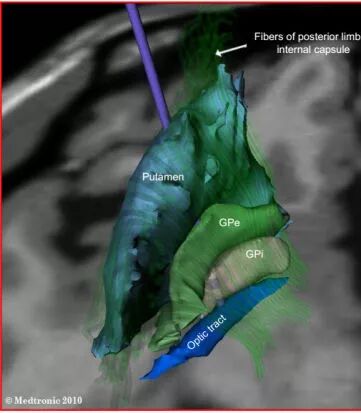

DBS手术是一个要求非常精准的手术,术中需要正好定位到相对应的大脑核团。在美国的时候美国的医师更多的选择GPI核团,国内选择STN核团的更多。

切开头皮、钻一个硬币大小的孔。术中使用微电极记录系统,记录不同核团的放电情况。

整个手术,我们通过术前计划系统、术中微电极记录、患者术中的症状缓解和植入后复查的影像学资料,4个方面保证电极精确的植入在相应的核团上。